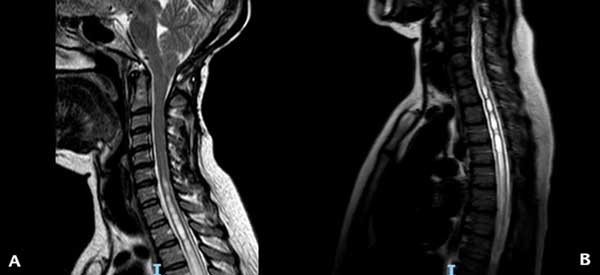

Figura 1. RM ponderada en T2 que muestra en (A) el descenso amigdalino y la siringomielia cervical y en (B) la extensión de la siringomielia a nivel torácico.

En el momento de la consulta, el examen físico presentó una leve paresia distal en ambos miembros superiores, hipoestesia termoalgésica en la mano y región subescapular izquierdas e hiperreflexia en ambos miembros inferiores. La resonancia magnética (RM) de encéfalo y columna cervical mostró un descenso marcado de las amígdalas cerebelosas con siringomielia cervicodorsal (Figura 1). Luego de la administración de contraste, se observó un refuerzo difuso de las meninges y senos venosos compatibles con hipotensión intracraneana (Figura 2). Ante la sospecha de una fístula espinal espontánea de LCR, se decidió realizar un estudio contrastado intratecal para determinar el sitio de la pérdida.